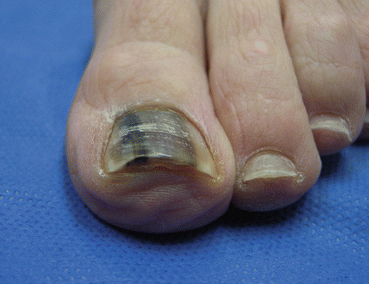

Patients most commonly present with a wartlike appearance of the nail bed with nail dystrophy [15]. Nail pigmentation with longitudinal melanonychia is common (Fig. 14.6) [18].

Fig. 14.6

Squamous cell carcinoma presenting with longitudinal melanonychia